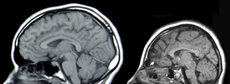

Mikrocefalie

Mikrocefalie je těžká vývojová porucha projevující se zakrněním/předčasným ukončením růstu mozku a obvykle i celé hlavy.

Další příčinou může být infekce matky virem zika během těhotenství. Hlavním příznakem je malý obvod lebky. Postižené děti mají obvykle také menší mozek. Mikrocefalie je často spojena s duševní a tělesnou poruchou. [1]